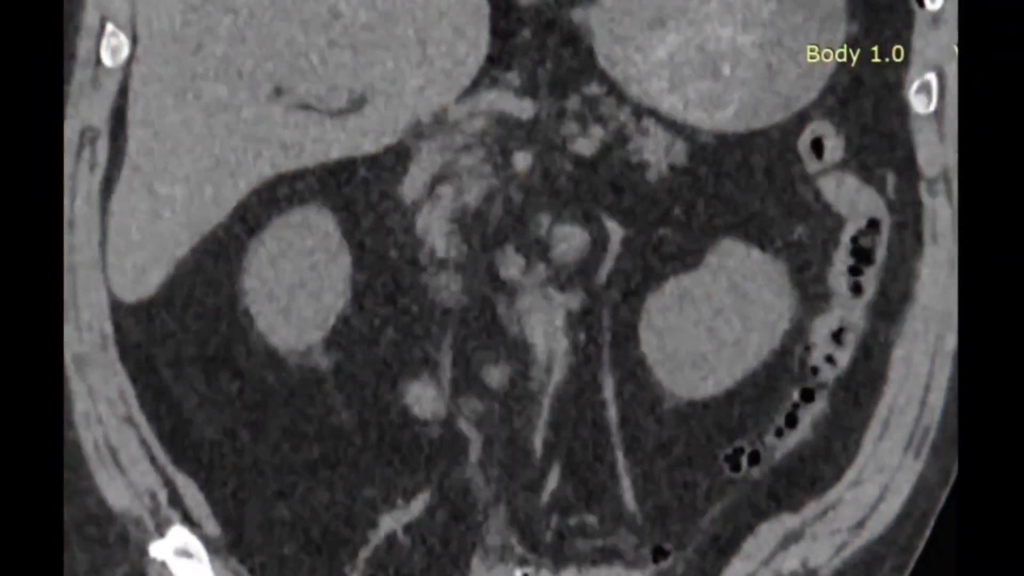

Безнефростомная супракостальная ПНЛ справа

29 авг 2025

Общая урология